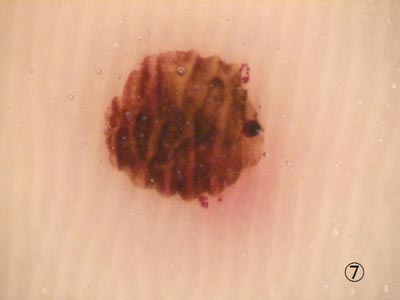

毛孔性紅色粃糠疹

Gビデオマイクロスコープは皮膚の炎症性病変の正確な診断にも活躍します。この病変は毛孔性紅色粃糠疹といって、皮膚の毛穴に一致して硬い炎症性のつぶつぶが生じるまれな疾患ですが、この様子が容易に確認できます。